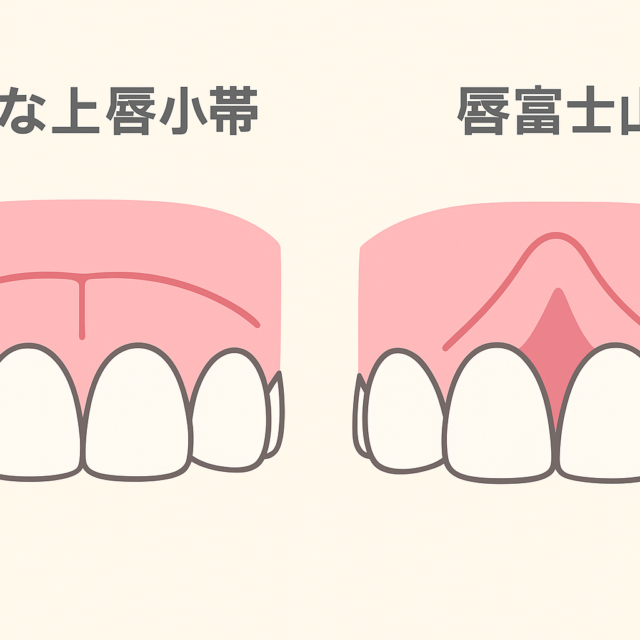

むし歯がなく歯医者に行くきっかけがない方・ご家族に入れ歯の方がいる・歯並びが悪い などです。